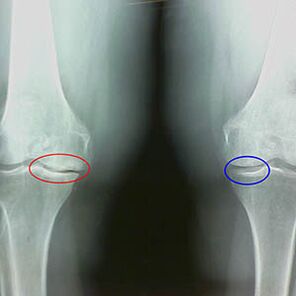

X -rays -x -x of the second stage of knee arthrosis:

- the pointed edges of the inter -chrus tuber tubers, where the cross -shaped ligament is attached;

- narrowing the joint gap on the medial side;

- The pointed edges of bone condyles on the medial sides, with less frequency on the side - depending on the development of the deformation of the Valgus or Vary joint.

For the second stage in LarsenThe narrowing of the joint gap in more than 50% is characteristic, but this can only be verified in the dynamics or comparison with a different joint.